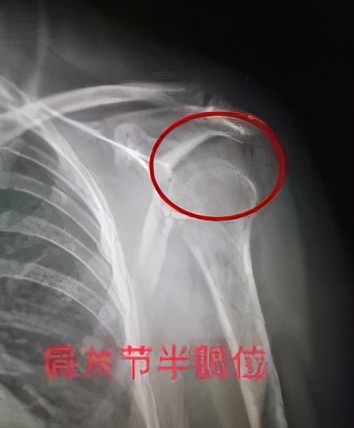

中风患者肩关节半脱位X线图

肩关节半脱位又称为不整齐肩,常见于偏瘫患者中。 主要表现为肱骨头下滑,肱骨头与肩峰之间会出现明显的空隙。肩关节半脱位起始阶段患者可能没有任何症状和不适感,当病程逐渐变长时,患侧上肢会慢慢出现被牵拉的不适感或疼痛,一旦出现肩关节半脱位多难以恢复,故了解其病因、加以保护、预防是必要的。